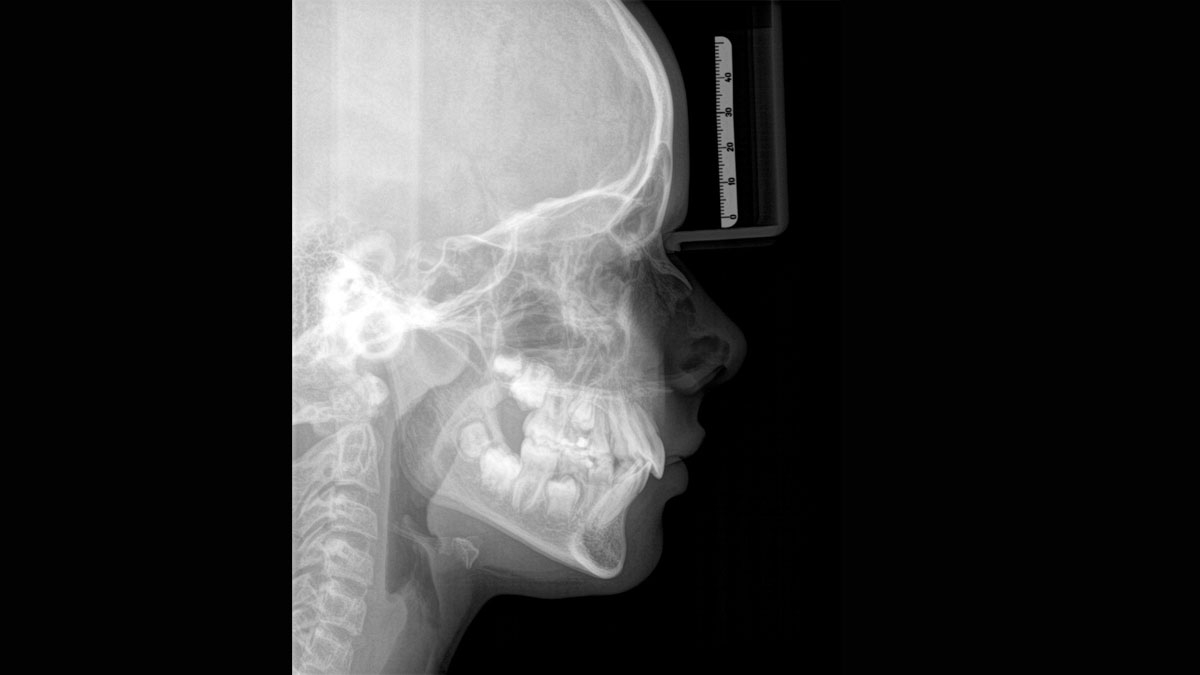

При помощи такого оборудования специалист сможет успешно решить широкий спектр диагностических и лечебных задач. Качественное изображение, достоверность при разноуровневой резкости (технология Sharp Layer), гибкий объём, 30 доступных вариантов цвета. Цефалометрическая визуализация позволяет получать боковые или симметричные снимки, а также определить положение при смещении зуба. Работая при разрешении до 80 мкм в режиме низкой дозы и HD, вы получаете качественные изображения выбранного формата, заботясь о комфорте и безопасности пациента.